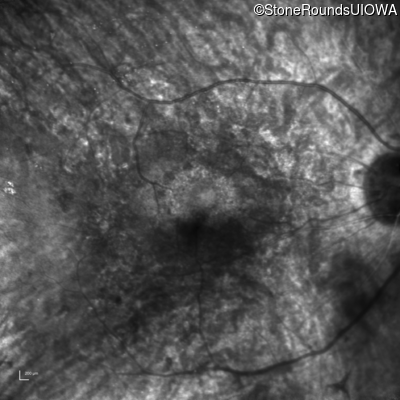

Infrared Fundus Photograph - Right - 20/50 +1

Exemplar